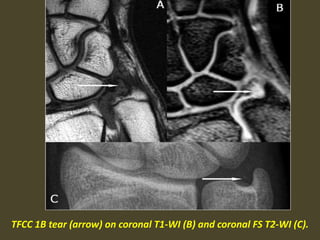

TFCC 1B tear (arrow) on coronal T1-WI (B) and coronal FS T2-WI (C).